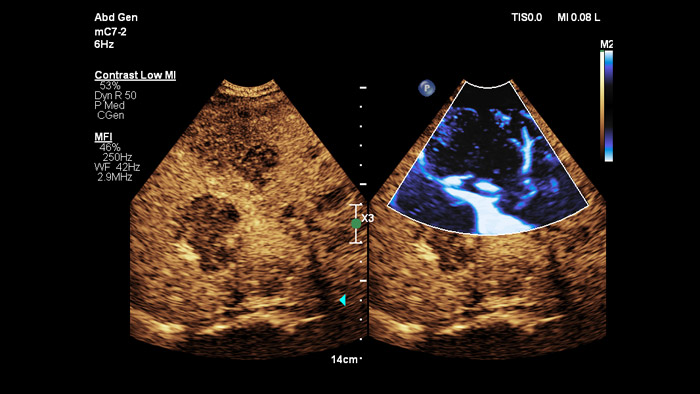

Treffen Sie auch in diagnostisch schwierigen Fällen die richtige Entscheidung mit den Philips Funktionen zur Bildfusion und Nadelnavigation. Ein effizienter Arbeitsablauf ermöglicht Klinikteams eine schnelle und effektive Fusion von CT/MRT/PET mit Live-Ultraschallbildern, wobei die Nadelnavigation die Biopsieführung bei kleinen, schwer zugänglichen Läsionen unterstützt.³

Mit der Tumorkontur können Anwender Läsionen mit einem halbautomatischen Tool planen und hervorheben. Es erleichtert das Zeichnen einer 3D-Kontur um die relevante Struktur und bietet so Unterstützung in schwierigen Fällen, bei denen die Läsion nicht einfach zu erkennen ist.